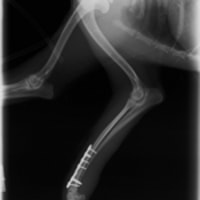

症例3:キルシュナーワイヤーのピンニングによる整復

ペルシャ猫 11ヶ月齢 雄

他院にて左大腿骨遠位の成長板骨折(salter-harrisⅠ型)が認められており、治療相談を目的として来院。当院にて、キルシュナーワイヤーを用いたピンニングにより骨折部位の整復を行いました。術後の経過は良好で、現在も経過観察中です。

術前レントゲン

術後レントゲン

Arthrex社のターゲティングデバイスを用いてピンニングの位置を調整することで、確実な固定を行っています。当院ではこの手術器具以外にも、人の手術にも使用される様々な器具を導入し、手術精度を高め、また医療メーカーと新しい器具の開発、試作にも取り組んでおります。